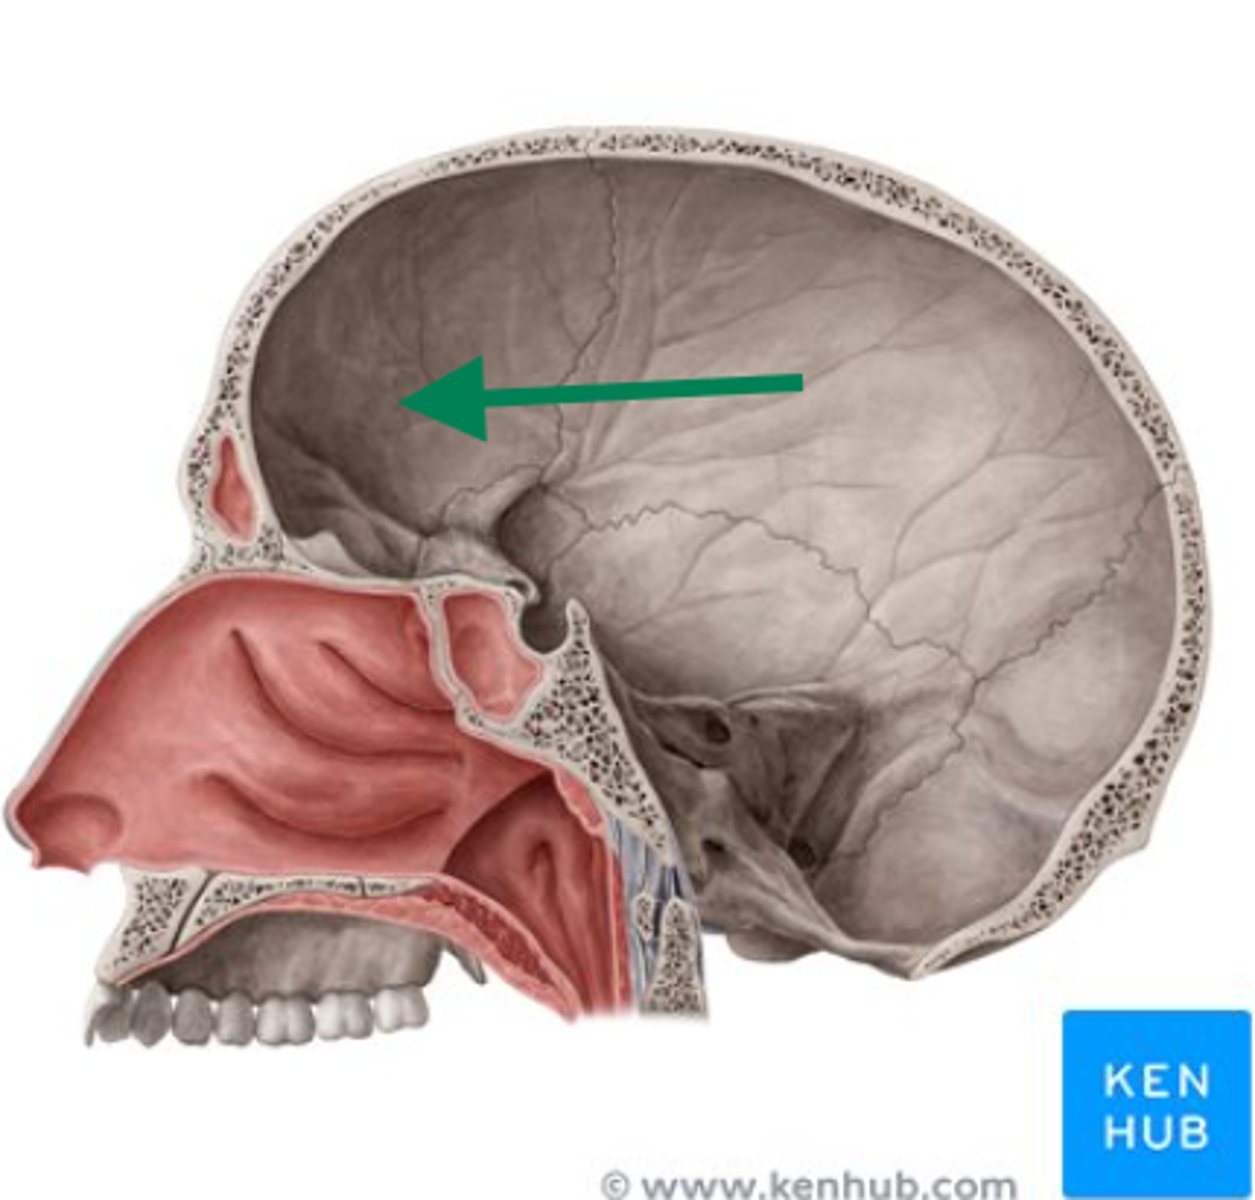

anterior cranial fossa